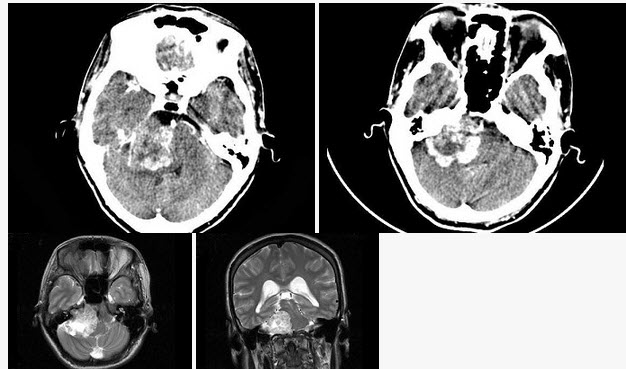

19、单项选择题

女,45岁,右侧听力下降伴行走不稳2个月,根据所提供图像,最可能的诊断是()

A.右侧脑膜瘤

B.右侧胆脂瘤

C.右侧皮样囊肿

D.右侧神经纤维瘤

E.右侧听神经瘤